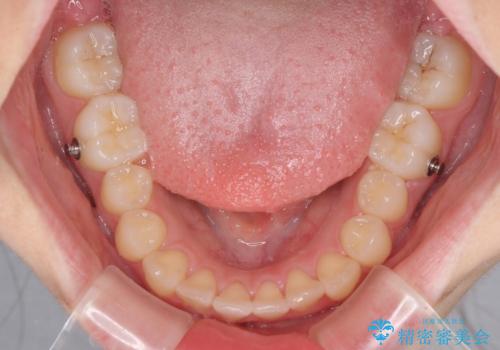

- 口元のデコボコを気にして来院された患者様です。

前歯の捻れにより口元が閉じにくくなっていたため、歯列全体の側方への拡大と、歯と歯の間を少し削ってスペースを獲得することとしました。

ゴムかけをしっかりと行ってもらい、スッキリとした口元に仕上げることができました。